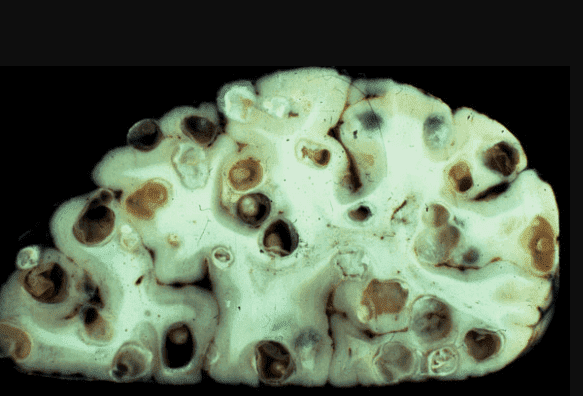

Мозок, уражений паразитами

На фото нижче можете побачити знімок кишечника. Пацієнтка померла від раку кишківника, спричиненого паразитами. Паразити отруюють здорові клітини своїми токсинами, через що вони змушені перероджуватися, змінювати свою структуру. І перероджуються вони саме в ракові клітини, які агресивніші й здатні протистояти паразитам. Але для людини ці клітини згубні. Пухлина швидко розвивається і метастазує. Людина гине протягом лічених місяців.

"Ходи" паразитів у просвіті кишечника